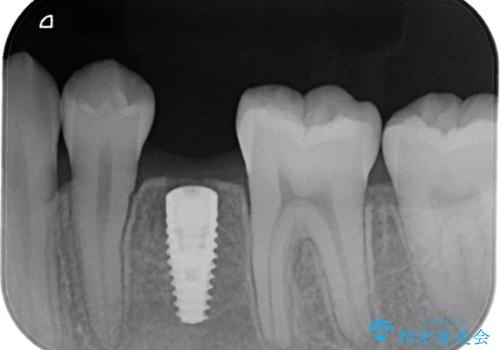

小臼歯のインプラント

- 小臼歯が先天性欠損していたため、インプラントにて補綴しています。

当院ではストローマンインプラントを導入しています。